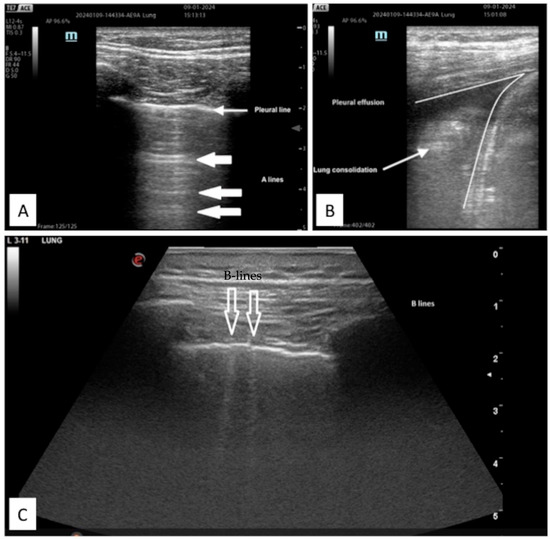

4.2.1. Protocols on Lung US

- -

- Abolition of lung sliding alone, sensitivity 100% specificity 78%;

- Absent lung sliding plus the A-line sign, sensitivity 95% specificity 94%;

- Lung point, sensitivity 79% specificity 100% [35].